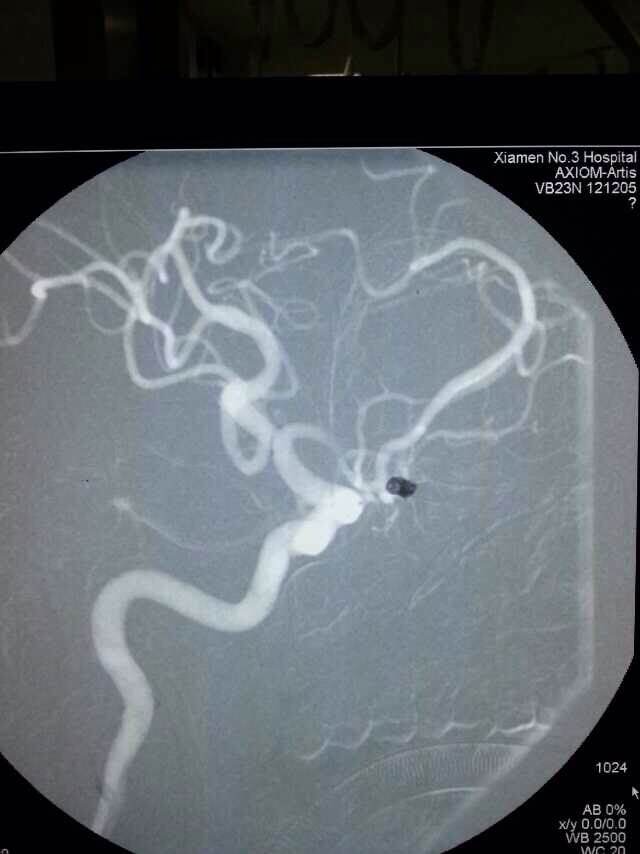

2014520是个特别的日子,第三医院手术室灯火通明,神经外科调集所有的技术团队手术一台接一台,有脑动脉瘤破裂的,有脑外伤出血的,忙碌不停。